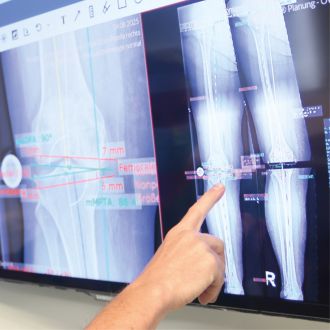

Hand zeigt auf eine digitale Röntgen- und Planungsdarstellung eines Kniegelenks auf einem Monitor.